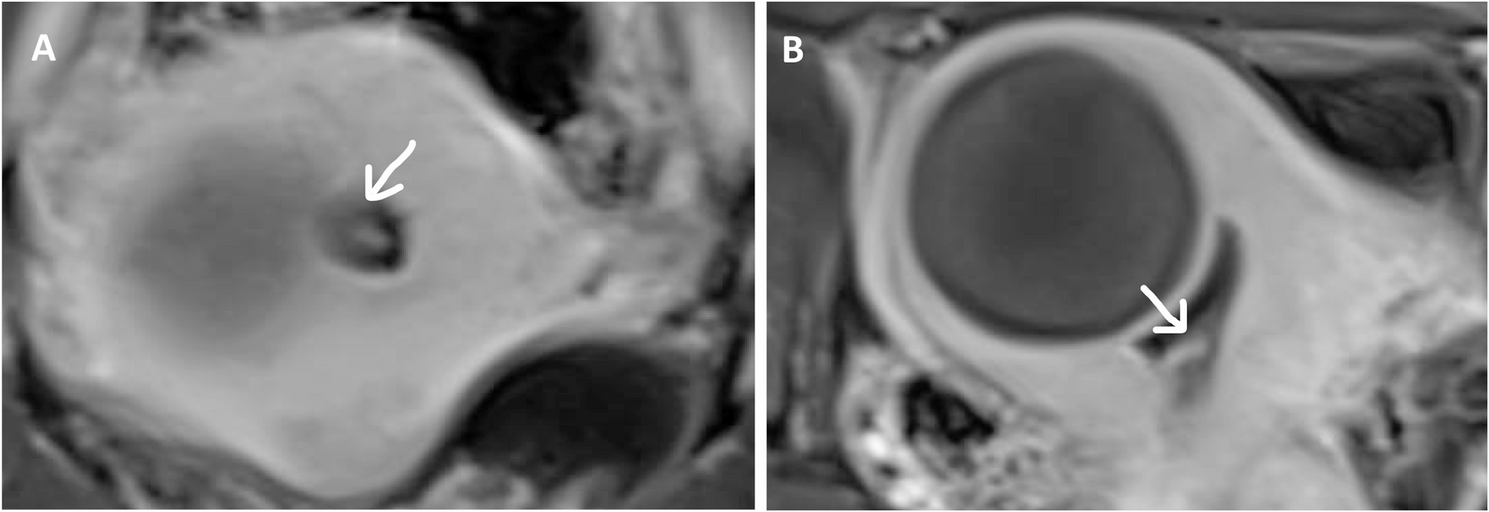

The patient underwent an evacuation of uterus using suction vacurette followed by gentle curettage under ultrasound guidance. The definitive histopathological exam confirmed product of conception (Fig. 2A) and also showed focal well-differentiated endometrioid adenocarcinoma (Fig. 2C) with background of endometrial hyperplasia with and without atypia (Fig. 2B). Staging MRI pelvis and CT chest and abdomen were performed which showed 1.5 × 0.7 × 0.7 cm lesion confined to the lower endometrial cavity (Fig. 3A and B) with no loco-regional involvement. Options of definitive surgery versus fertility sparing management were discussed with patient. The patient opted for definitive surgery as she had completed her family and was not keen for future fertility. The case was discussed at a multidisciplinary tumor board meeting and the board recommended to proceed with definitive surgery as patient was not keen for fertility preservation. She underwent total laparoscopic hysterectomy (TLH), bilateral salpingectomy and bilateral sentinel lymph node (SLN) biopsy with ovarian conservation. She recovered well and was discharged on post-operative day 2. The final histology showed no evidence of residual adenocarcinoma. There was a focus of complex hyperplasia without atypia and a focus of complex atypical hyperplasia. Immunological staining reveled positive staining for ER and wild type P53. Peritoneal washing was negative and lymph nodes were not involved. Ancillary studies were performed on the original specimen from dilatation and curettage as endometrial carcinoma was absent on the final hysterectomy specimen. Immunohistochemistry for DNA mismatch repair protein returned normal and there was no microsatellite instability. The case was discussed at the multidisciplinary tumor board and was staged as stage 1 A grade 1 endometrioid adenocarcinoma of the uterus. Patient remained disease-free at 21-months follow-up.

Fig. 3

MRI pelvis post evacuation of uterus. 1.5x0.7x0.7cm endometrial tumor in the lower endometrial cavity, without myometrial invasion. A. Axial view of the endometrial cavity.B. Coronal view of the endometrial cavity